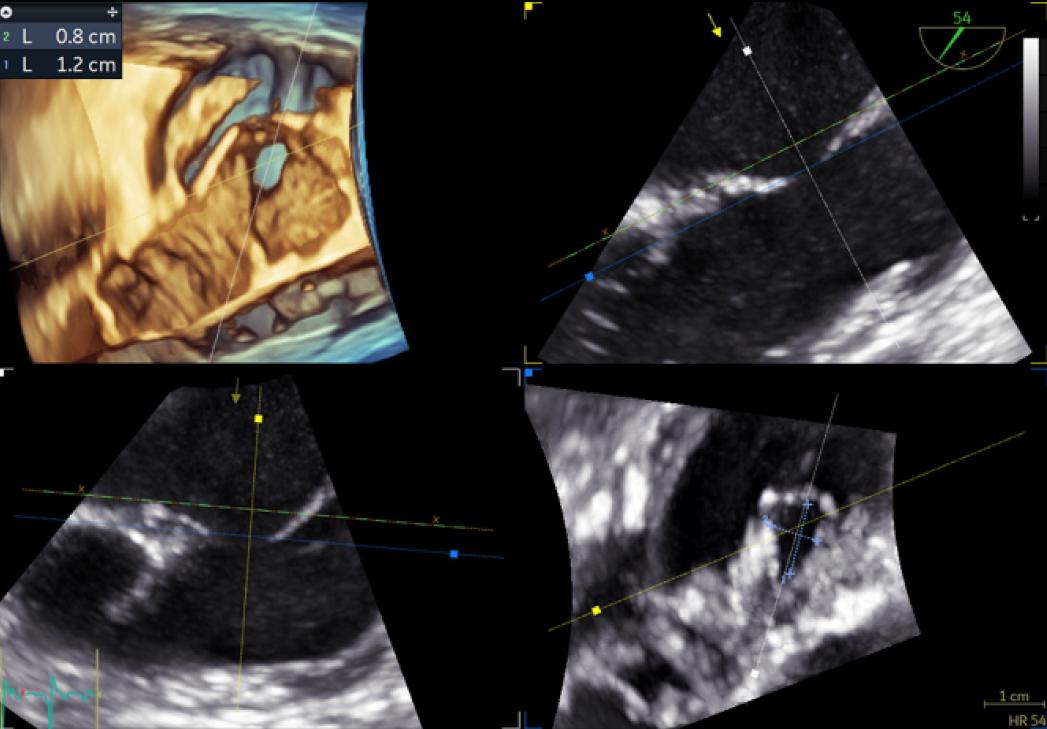

Figure 1